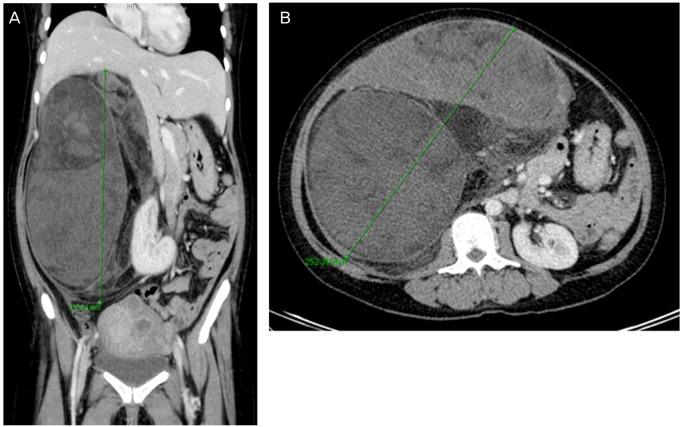

A 39-year-old woman was referred to our hospital at 28+2 week gestation. Routine obstetric examination revealed a palpable pelvic mass. Initial investigation by magnetic resonance imaging demonstrated a huge solid mass with heterogeneous enhancement that completely filled the right side of the abdomen. She underwent two surgeries: a programmed cesarean section by Department of Obstetrics and Gynecology team and a laparotomy performed by the General Surgery team. Final diagnosis was de-differentiated liposarcoma (French Federation Nationale des Centres de Lutte Contre le Cancer grade 2/3). She has been treated with radiation therapy focusing on high risk area of retroperitoneum followed by adjuvant chemotherapy (doxorubicin and ifosfamide). Below is the full case with literature review.

一名39岁女性在妊娠28 + 2周时被转诊至我院。常规产科检查发现盆腔可触及肿块。磁共振成像初步检查显示一个巨大的实性肿块,增强不均匀,完全占据了腹部右侧。她接受了两次手术:妇产科团队进行的计划性剖宫产以及普通外科团队进行的剖腹手术。最终诊断为去分化脂肪肉瘤(法国国立癌症中心联合会2/3级)。她接受了针对腹膜后高危区域的放射治疗,随后进行辅助化疗(多柔比星和异环磷酰胺)。以下是完整病例及文献综述。